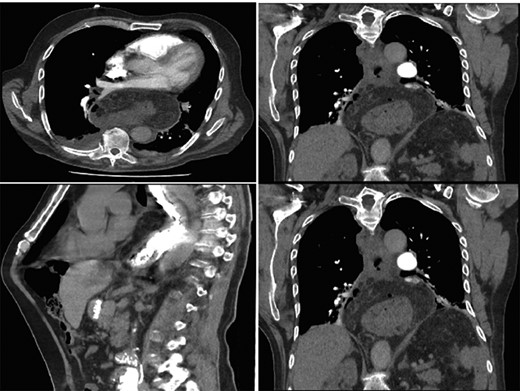

On assessment, he was hypertensive, normal heart rate and temperatures. Abdominal exam was unremarkable. Laboratory tests were all within normal range. CT Abdomen showed distal esophageal mural thickening suggestive of esophagitis in small hiatus hernia with bilateral pleural effusions (Fig. 5).